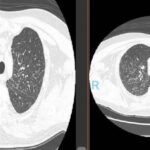

La sarcoidosis pulmonar se caracteriza por varios hallazgos en la tomografía computarizada de alta resolución (TCAR). Estos incluyen linfadenopatía hiliar y paratraqueal bilateral bien definida, opacidades nodulares y micronodulares con distribución perilinfática. Los nódulos son redondeados y suelen tener un tamaño de 2 a 4 mm. También se observa el agrandamiento y calcificación de los ganglios linfáticos hiliares bilaterales. Las calcificaciones pueden presentar diferentes aspectos, como amorfo, puntiforme (parecido a una palomita de maíz) o similar a una cáscara de huevo. La distribución perilinfática de las lesiones micronodulares es el patrón parenquimatoso más frecuente. Con el tiempo, estas lesiones pueden fusionarse y formar macronódulos y conglomerados similares a masas, con la presencia de pequeños nódulos satélites alrededor de las masas conglomeradas, lo que se conoce como “signo de galaxia”.

En la TCAR se pueden encontrar otros hallazgos menos frecuentes, como cambios fibróticos con opacidades lineales y bronquiectasias por tracción, opacidades parcheadas en vidrio esmerilado, consolidación parcheada del espacio aéreo (alveolitis sarcoide o sarcoidosis alveolar), opacidades reticulares lineales aisladas, halo inverso o signo del atolón. La sarcoidosis pulmonar también muestra un patrón de atenuación en mosaico debido a la afectación granulomatosa o fibrosis de las vías respiratorias pequeñas, lo cual puede estar asociado con obstrucción en las pruebas de función pulmonar. El atrapamiento de aire es común pero no específico de la sarcoidosis y puede estar presente en cualquier etapa radiográfica de la enfermedad. Se detectan anomalías traqueobronquiales en la TC, con engrosamiento y estenosis de la pared bronquial, que se correlacionan con los hallazgos broncoscópicos.

La estenosis bronquial puede ser causada por acumulación de granulomas endobronquiales, compresión extrínseca de las vías respiratorias debido a ganglios linfáticos agrandados en el mediastino, o distorsión de los bronquios debido a enfermedad parenquimatosa fibrótica en etapa terminal. El bronquio del lóbulo medio derecho es el más afectado en la sarcoidosis. En casos avanzados y de alto riesgo, la TCAR puede mostrar quistes fibróticos, ampollas y enfisema paracicatricial, que indican una etapa avanzada de la sarcoidosis. Estas lesiones tienden a afectar las zonas pulmonares superiores y medias, siguiendo las vías respiratorias más grandes en una distribución perihiliar. Los cambios quísticos subpleurales en panal se encuentran principalmente en las zonas pulmonares superiores y medias, mientras que las bases pulmonares se ven menos afectadas. Se debe considerar la fibrosis pulmonar idiopática en el diagnóstico diferencial cuando las bases pulmonares están involucradas.

En la tomografía computada de tórax en ventana pulmonar se identifica un patrón micronodular con distribución perilinfática y difusa en ambos hemitórax. Este hallazgo se acompaña de un engrosamiento peribronquial notable, así como de opacidades en vidrio deslustrado, que predominan en las zonas subpleurales y en las regiones posteriores de ambos pulmones.